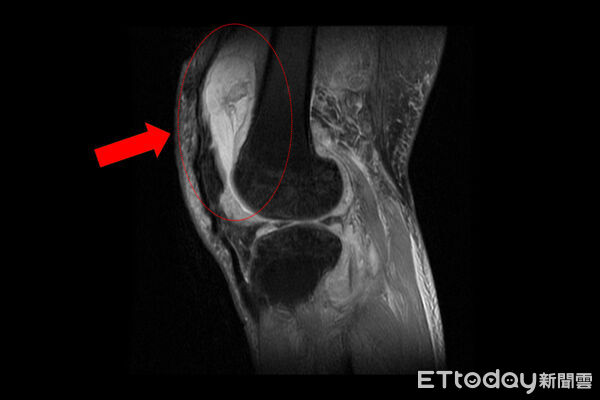

▲一名患者膝關節疼痛,竟是「肺外結核感染」。(圖/院方提供,下同)

台中慈濟醫院關節中心主任周立展指出,該患者長期左膝腫痛、幾乎無法行走,以為只是退化性關節炎,服用止痛藥、抽關節積水、熱敷復健,但卻越來越嚴重,就醫時膝蓋已腫脹無法彎曲,化驗後發現白血球數值雖偏高,但並非典型的細菌感染,懷疑有其他原因,進一步X光與磁振造影檢查,顯示膝蓋內已有大量積液並化膿,屬於嚴重關節感染。